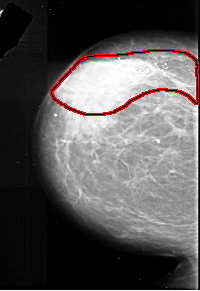

A_1017_1.LEFT_MLO

LEFT_MLO LINES 5866 PIXELS_PER_LINE 3466 BITS_PER_PIXEL 16 RESOLUTION 42 OVERLAY

FILE: A_1017_1.LEFT_MLO.OVERLAY

TOTAL_ABNORMALITIES 1

ABNORMALITY 1

LESION_TYPE CALCIFICATION TYPE PLEOMORPHIC DISTRIBUTION SEGMENTAL

ASSESSMENT 5

SUBTLETY 5

PATHOLOGY MALIGNANT

TOTAL_OUTLINES 1

BOUNDARY